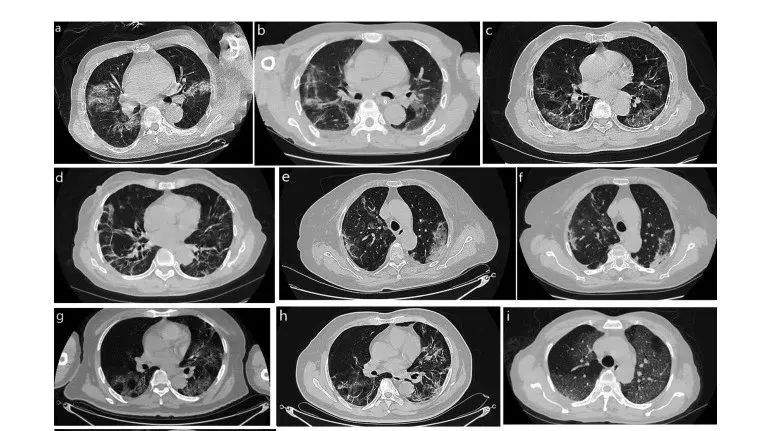

干細(xì)胞,尤其是間充質(zhì)干細(xì)胞(MSCs),具有強(qiáng)大的免疫調(diào)節(jié)和組織損傷修復(fù)功能。自新冠肺炎疫情爆發(fā)以來(lái),間充質(zhì)干細(xì)胞 (MSC) 療法也一直備受關(guān)注。目前的研究表明,間充質(zhì)干細(xì)胞可有效減輕SARS-CoV-2引起的患者嚴(yán)重炎癥反應(yīng),減輕肺損傷,改善肺功能,保護(hù)和修復(fù)肺,在緩解新冠肺炎引起的肺纖維化方面發(fā)揮積極作用。

在國(guó)內(nèi),由上海大學(xué)、首都醫(yī)科大學(xué)、鄭州大學(xué)第一附屬醫(yī)院等多家機(jī)構(gòu)合作發(fā)表的論文顯示,間充質(zhì)干細(xì)胞移植療法改善了新型冠狀病毒肺炎(COVID-19)患者的預(yù)后,患者的肺功能和癥狀在間充質(zhì)干細(xì)胞移植后2天有明顯改善。